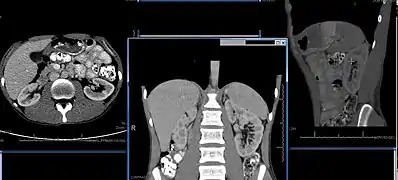

Normal adult right kidney as seen on abdominal ultrasound with a pole to pole measurement of 9.34 cm.

Renal ultrasonography is essential in the diagnosis and management of kidney-related diseases.[39] Other modalities, such as CT and MRI, should always be considered as supplementary imaging modalities in the assessment of renal disease.[39]